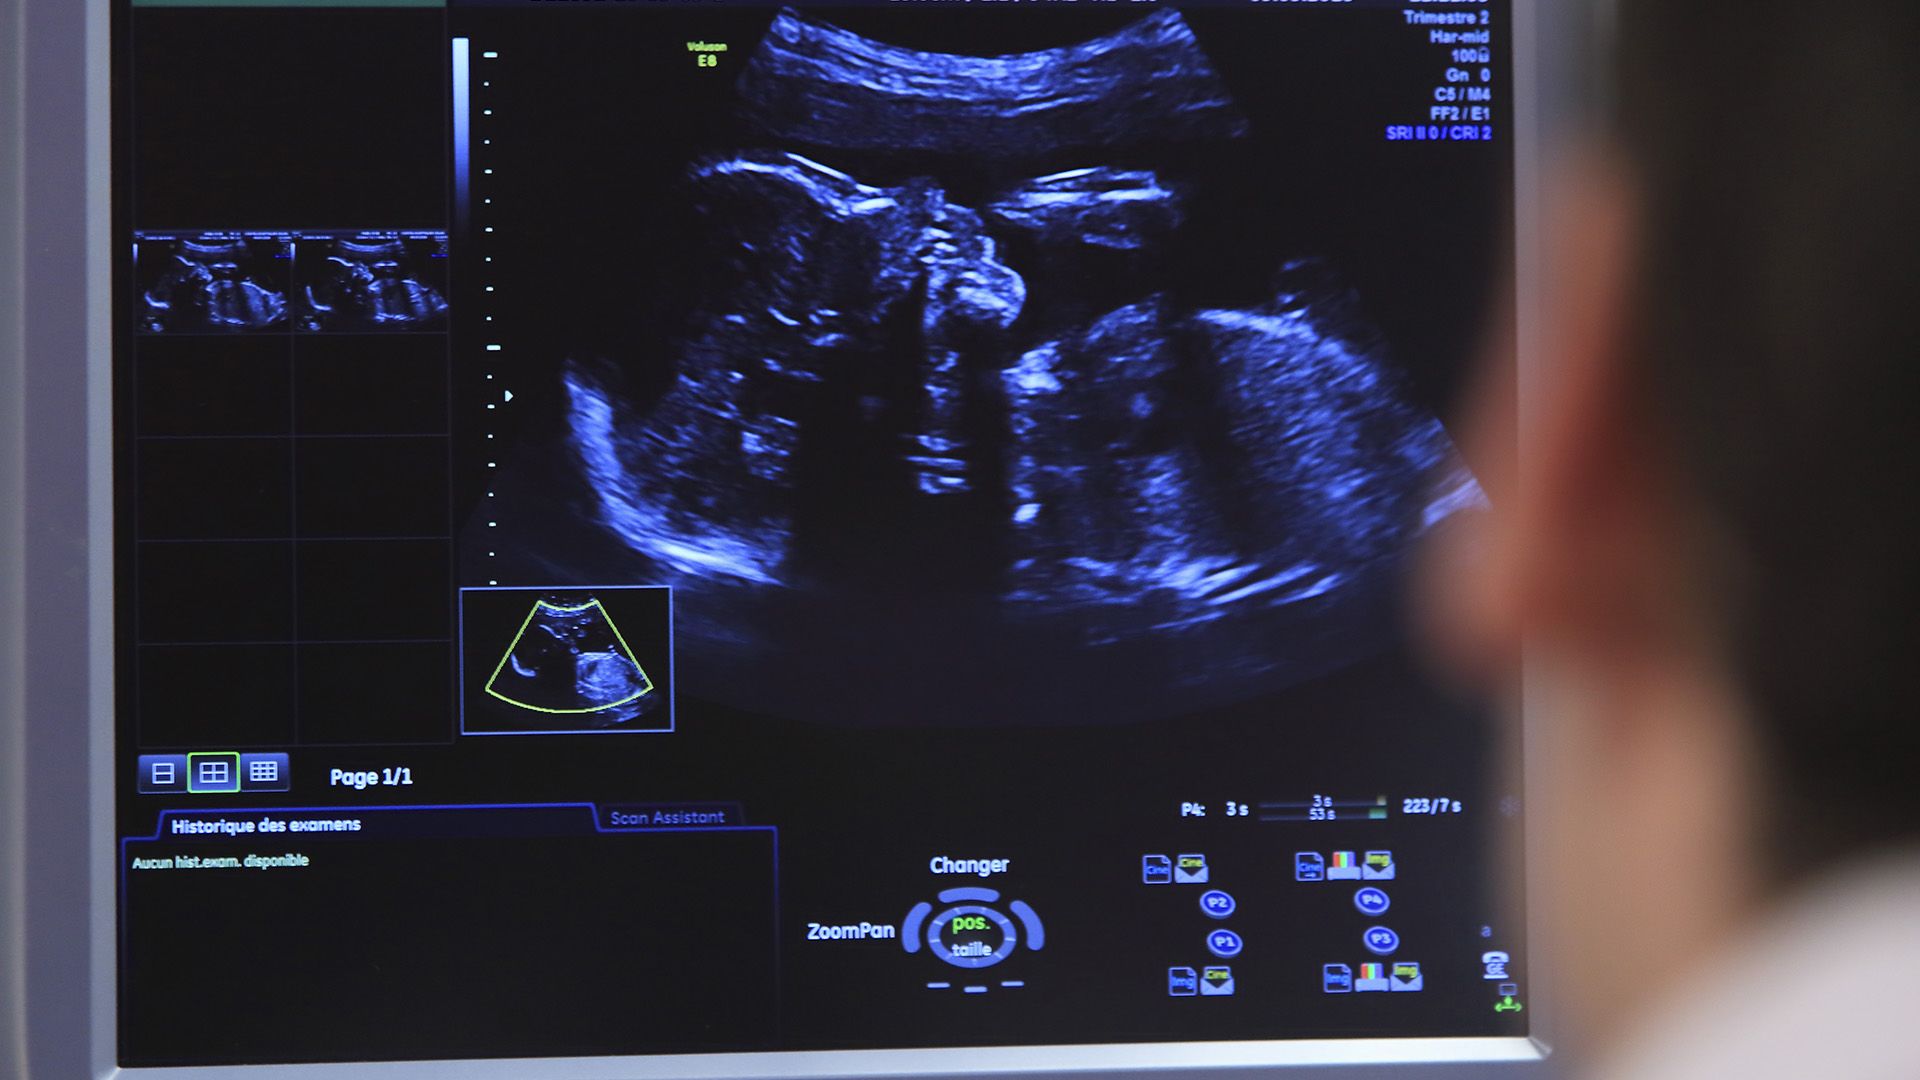

Sokkoló: a „boldog babáról” egy rutinvizsgálaton derült ki, hogy leukémiás